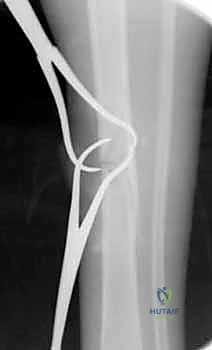

تُعتبر كسور عظم الساق (الظنبوب - Tibia) من أكثر إصابات العظام الطويلة شيوعًا وتعقيدًا في ممارسة جراحة العظام (Orthopedic Surgery) على مستوى العالم. يمثل عظم الساق الدعامة الأساسية التي تحمل الغالبية العظمى من وزن الجسم، وتنقل القوى الحركية والميكانيكية من الركبة إلى الكاحل والقدم أثناء المشي والجري والوقوف.

نظرًا لموقعه التشريحي السطحي جداً (حيث يقع تحت الجلد مباشرة في الجزء الأمامي من الساق دون غطاء عضلي كثيف يحميه)، فإنه يكون عرضة بشكل كبير للإصابات المباشرة وغير المباشرة. هذه الهشاشة التشريحية تجعل كسور الساق غالباً مصحوبة بإصابات في الأنسجة الرخوة المحيطة (الجلد، الأوعية الدموية، والأعصاب)، مما يزيد من تعقيد الحالة ويستوجب تدخلاً طبياً عالي الاحترافية.

الأعراض والعلامات السريرية: كيف تعرف أنك مصاب بكسر في الساق؟

- تشوه واضح في الساق: قد تبدو الساق ملتوية، أو أقصر من الطبيعي، أو بها انحناء غير طبيعي (Deformity).

- تورم سريع وكدمات: انتفاخ ملحوظ في مكان الإصابة مع ظهور تغير في لون الجلد (ازرقاق أو احمرار) نتيجة النزيف الداخلي.

- بروز العظم (في الكسور المفتوحة): في الحالات الشديدة، قد يخترق العظم المكسور الجلد ويكون مرئياً للعين المجردة، وهي حالة طوارئ طبية قصوى تستوجب تدخلاً جراحياً فورياً لمنع التلوث البكتيري.